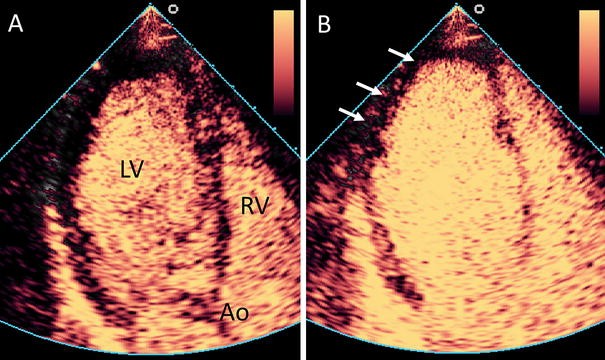

Assessment of myocardial perfusion using CEUS. Example of an abnormal myocardial perfusion echocardiogram. a Apical three chamber view. After administration of the contrast agent, a high mechanical index flash is given to destroy the contrast agent that is present in the myocardium. Thereafter, the left ventricular myocardium does contain no or only a limited amount of contrast agent. Ao aorta, LV left ventricle, RV right ventricle. b After a short period, the myocardium is filled with blood and contrast agent. There is an apical and lateral perfusion defect visible (arrows), indicating a significant coronary stenosis. Example reproduced from [84]